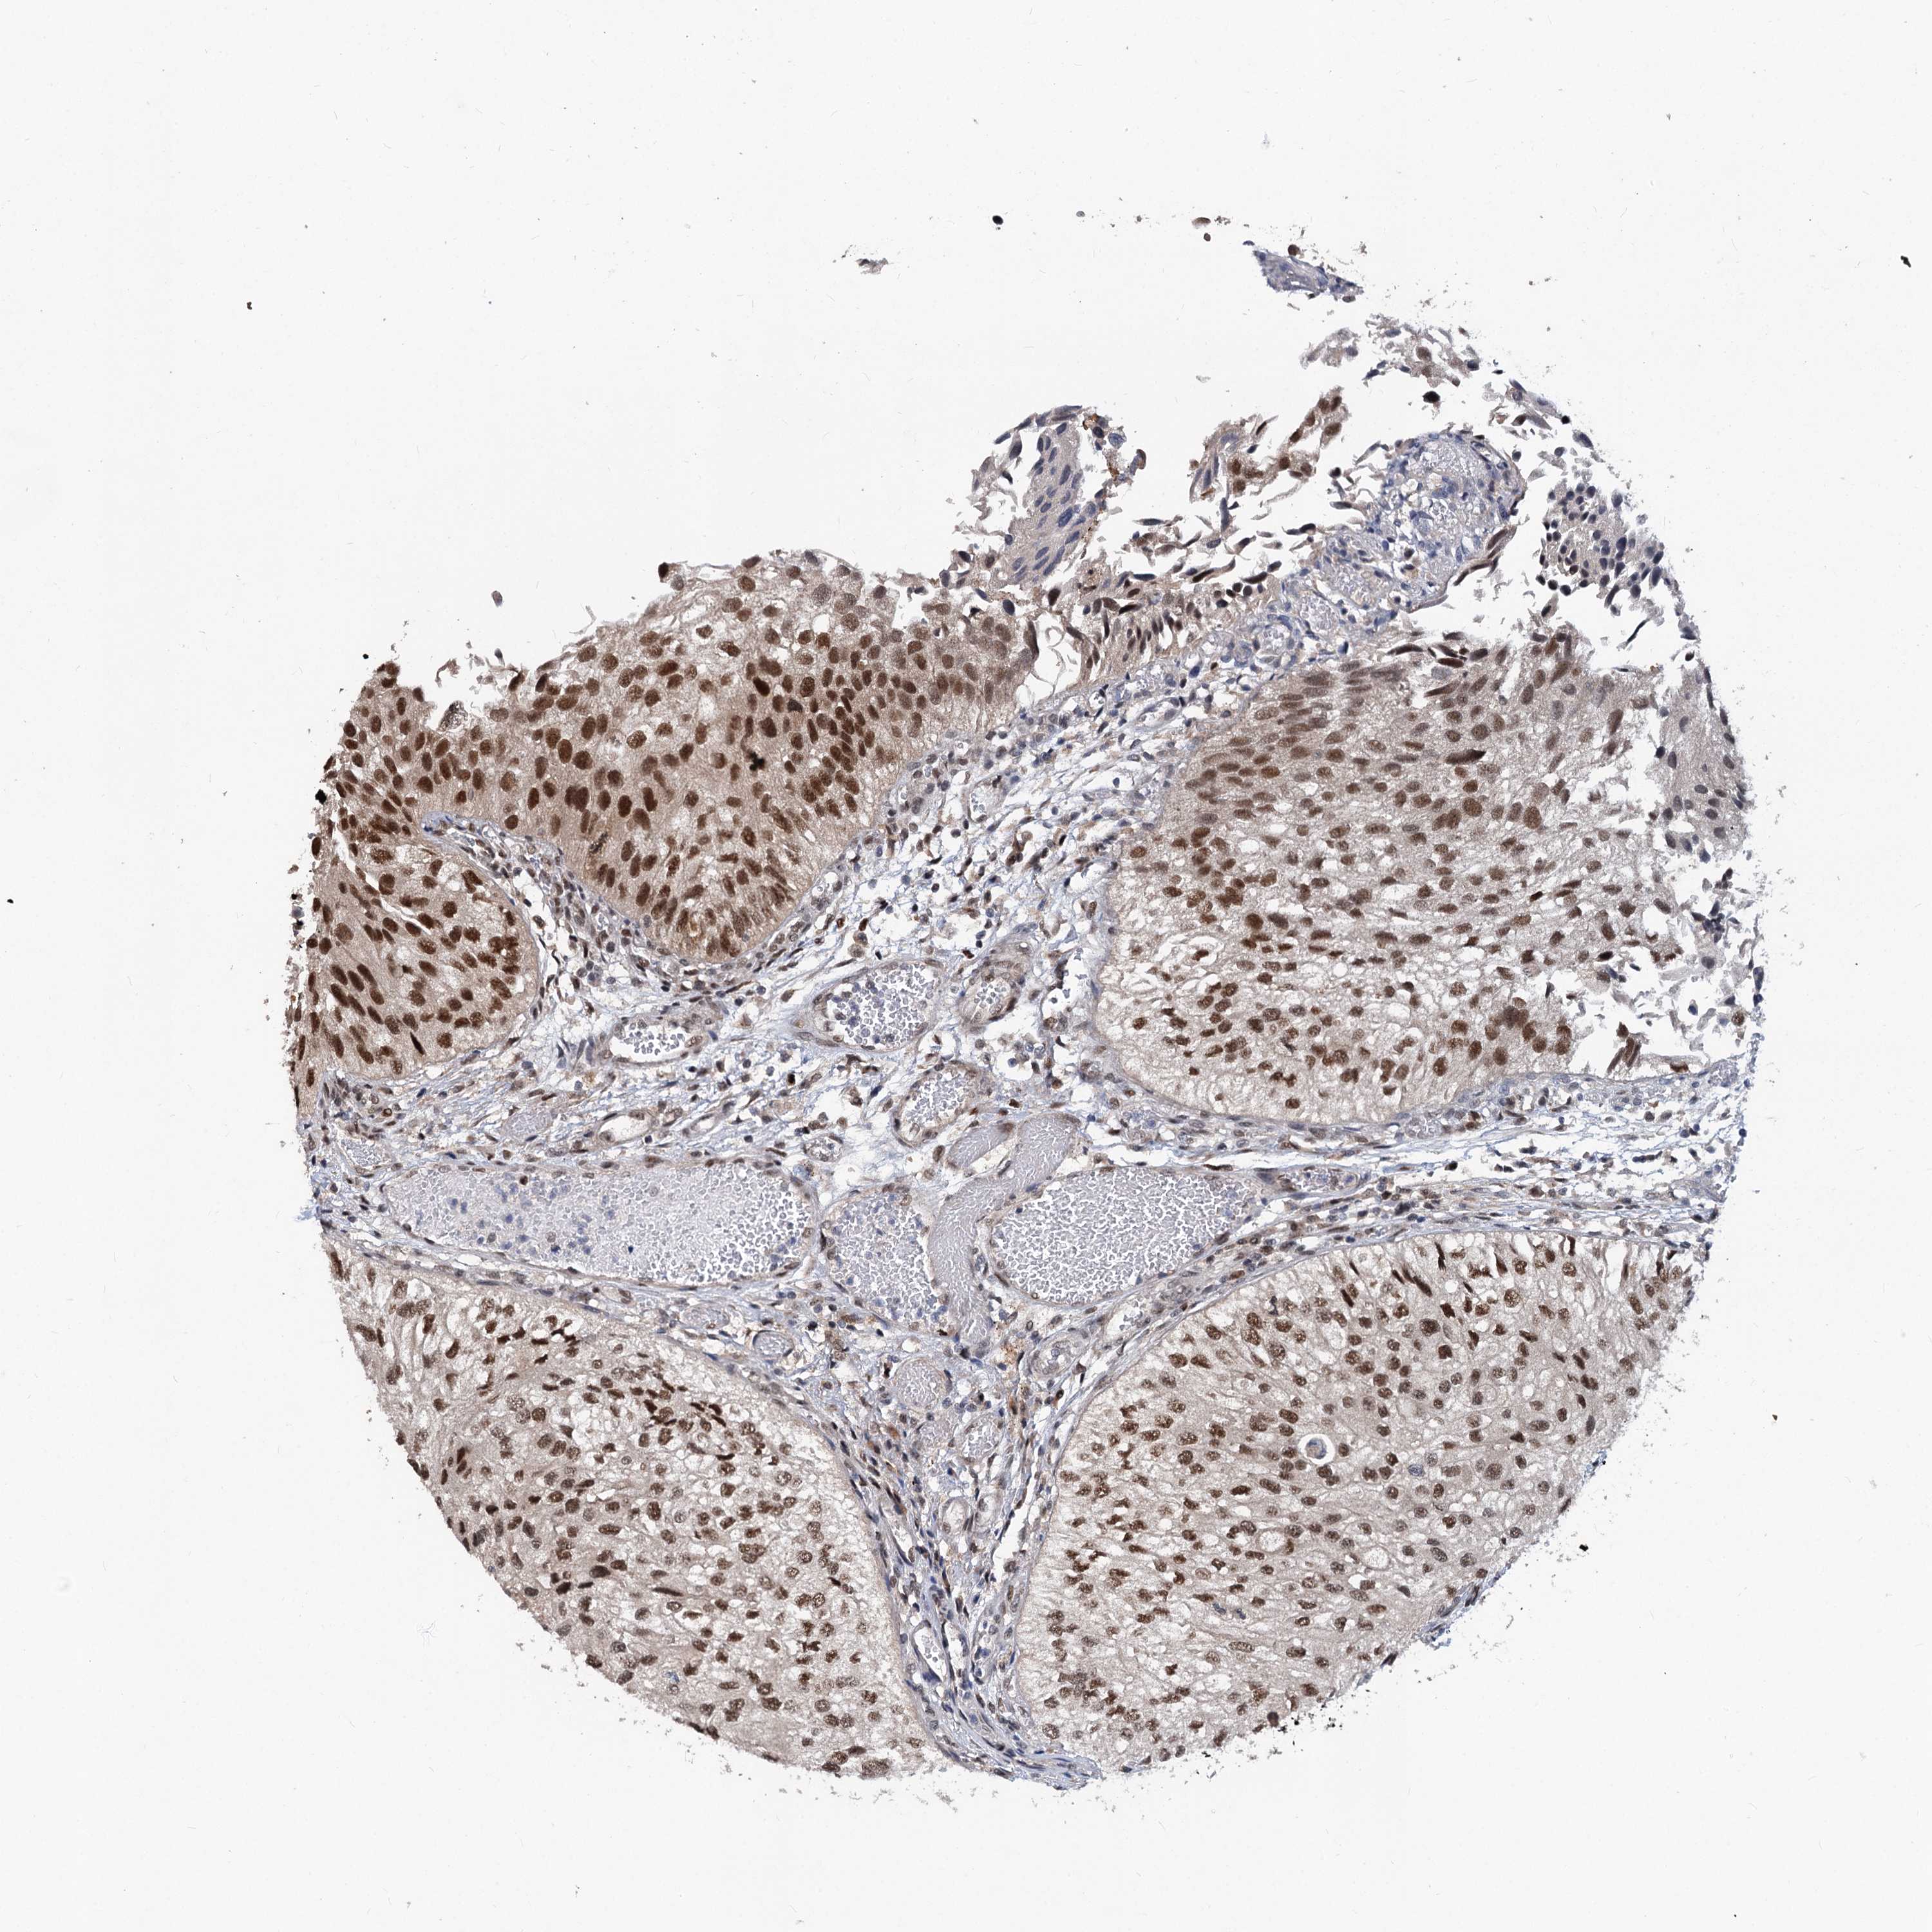

UROTHELIAL CANCER - Protein expressioni

A mouse-over function shows sample information and annotation data. Click on an image to view it in a full screen mode. Samples can be filtered based on level of antibody staining by selecting one or several of the following categories: high, medium, low and not detected. The assay and annotation is described here.

Note that samples used for immunohistochemistry by the Human Protein Atlas do not correspond to samples in the TCGA dataset.

Antibody stainingi

Antibody staining in the annotated cell types in the current human tissue is reported as not detected, low, medium, or high, based on conventional immunohistochemistry profiling in selected tissues. This score is based on the combination of the staining intensity and fraction of stained cells.

Each image is clickable and will lead to virtual microscopy that enables deeper exploration of all samples and also displays staining intensity scores, fraction scores and subcellular localization as well as patient and tissue information for each sample.

Antibody HPA038779

Staining

High

Medium

Low

Not detected

Intensity

Strong

Moderate

Weak

Negative

Quantity

>75%

75%-25%

<25%

None

Location

Nuclear

Cytoplasmic/membranous

Cytoplasmic/membranous,nuclear

Urothelial carcinoma, High grade

Urothelial carcinoma, Low grade